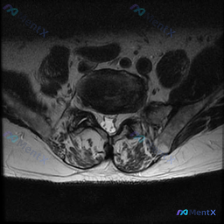

刚整理了一份很典型的腰椎椎间盘病变MRI读片资料,分享给大家,顺便把分析思路理一遍。 病例影像基础信息 这是一份腰椎MRI T2加权轴位(横断面)影像,显示腰椎管层面,可见椎体后缘、椎间盘、硬膜囊、侧隐窝、后方椎板及关节突关节等结构,图像对比度正常,脑脊液呈高信号。 核心阳性征象 1. 椎间盘:髓核...

病例分析:临床疑诊椎间盘病变,影像却未见明确突出 今天整理了一份有意思的病例讨论素材,核心矛盾是临床怀疑椎间盘病变,单一层面影像却没有发现明确的结构性病变,把完整思路分享给大家。 一、影像基本信息 这是一张腰椎MRI T2加权轴位图像,结合解剖结构判断为腰椎下段椎间盘层面,我们先来看具体的影像表现:...